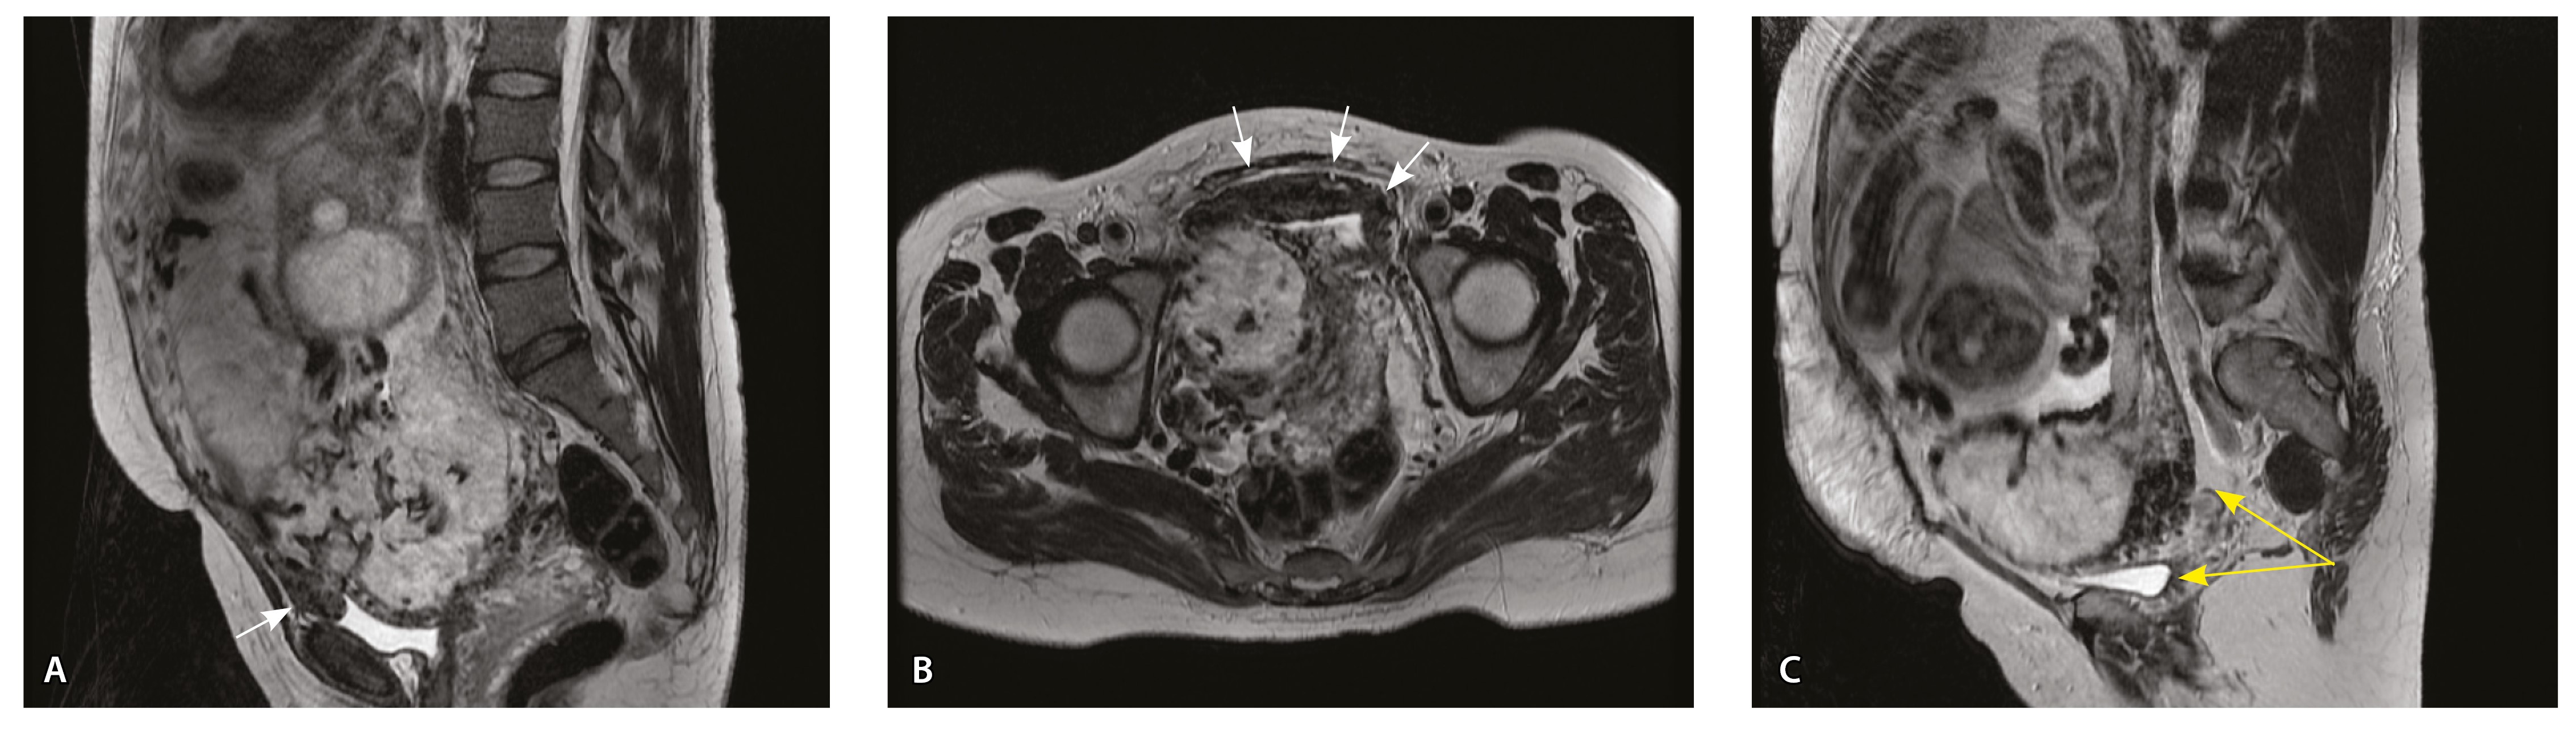

Сосуды 2-го типа. Единичные сливающиеся сосудистые полости в маточно-плацентарной области, мелкие ретроплацентарные гематомы, участки с белковым содержимым по МР-сигналу в зоне контакта ворсин со стенкой матки (рис. 4).

Рис. 4. Беременность 32 недели, pl. accreta, PAS 1 по FIGO. На магнитно-резонансных томограммах в режиме Т2-взвешенного изображения в сагиттальной (А) и аксиальной (Б) плоскостях видны сосуды на границе маточно-плацентарной области, сливающиеся между собой (белые стрелки), без выраженного дефицита толщины миометрия и рубца от кесарева сечения, без признаков выбухания стенки матки. На Т1-взвешенном изображении в режиме подавления сигнала от жировой ткани в аксиальной плоскости (В) выявляется наличие участков повышенного сигнала (желтые стрелки) на границе маточно-плацентарной области, что соответствует геморрагическому компоненту в подострой/хронической стадии (ретроплацентарные гематомы) либо белковому содержимому (фибриноид)

Сосуды 5-го типа. Наличие гиперваскуляризации за пределами матки по данным МРТ, на границе с мочевым пузырем с вовлечением его стенки, сосуды в области перешейка матки, параметрия, в том числе в сочетании с признаками фиброза, наличием рубцово-спаечных изменений и др. Можно предположить, что сосуды 5-го типа являются аналогом pl. рercreta PAS 3b, 3c (рис. 15).

Рис. 15. Беременность 34 недели, pl. percreta, PAS 3b по FIGO (A, Б), PAS 3c по FIGO (В). На магнитно-резонансных томограммах в режиме Т2-взвешенного изображения в сагиттальной (A, В) и аксиальной (Б) плоскостях определяется гиперваскуляризация в области выраженно истонченного нижнего маточного сегмента с распространением сосудов на заднюю стенку мочевого пузыря в области дна (белые стрелки), в область перешейка матки (желтые стрелки)